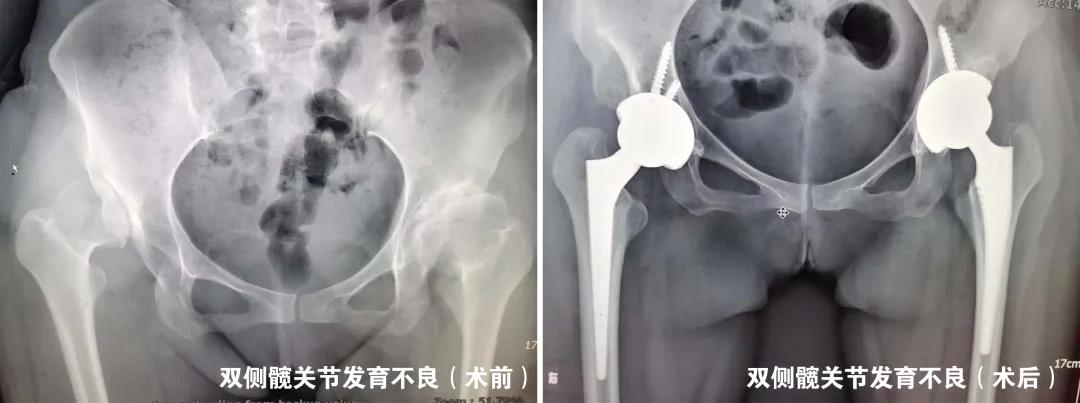

我们根据股骨头坏死的分期不同,根据患者病情“量体裁衣”制定个体化方案,除常规开展微创精准减压治疗股骨头坏死外,对于中末期股骨头坏死即髋关节发育不良导致的继发性股骨头坏死及骨关节炎行全髋关节置换术亦取得了良好的手术效果。